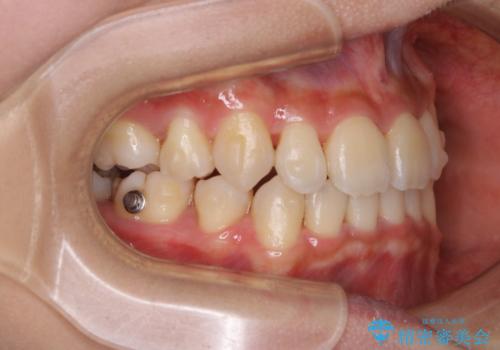

- 元々は海外でワイヤー矯正を行っていたが、コロナ禍で海外への往来が難しくなり、治療を中断せざるを得なくなってしまった方です。

ご本人のご希望により、インビザラインによる治療を行いました。

- インビザラインFULL

ブラケット除去直後に目立っていた下顎前歯部の大きなブラックトライアングルもあまり目立たなくなり、大変喜んでいただけました。